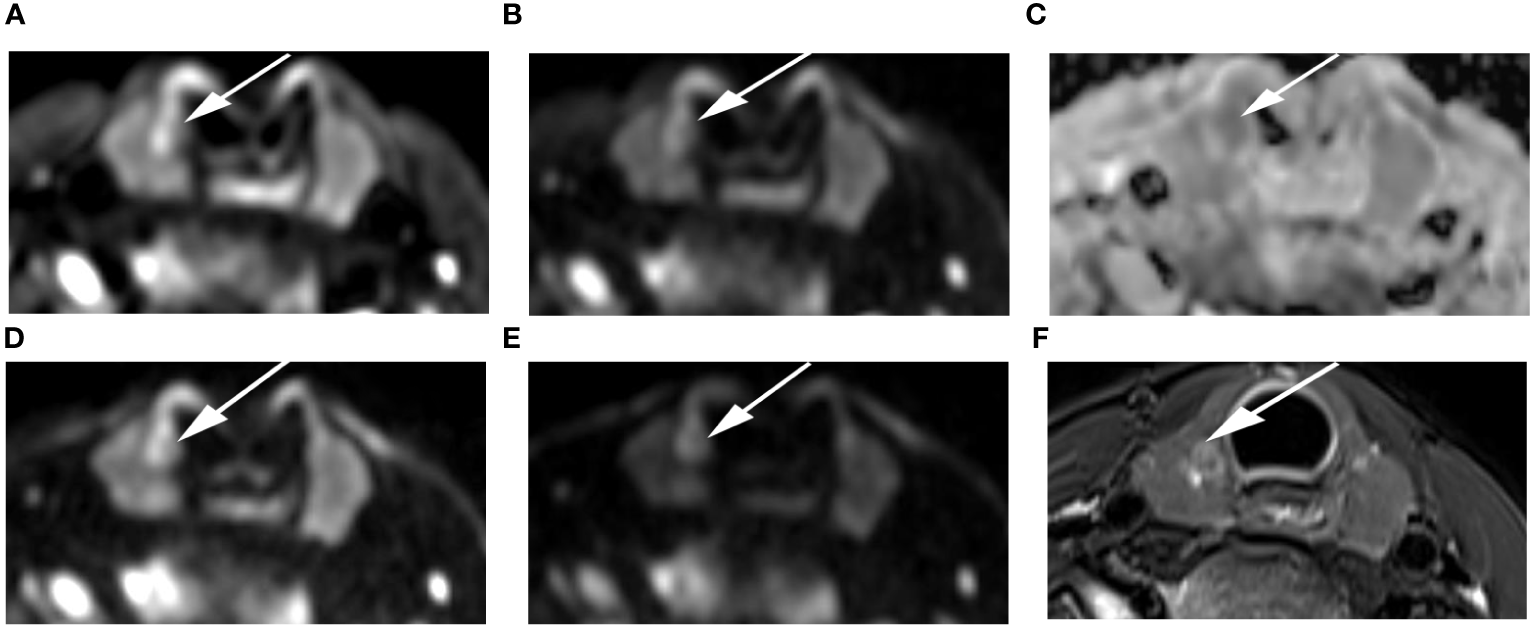

Figure 4 Images of a 55-year-old female with left lobe nodular goiters (arrow): DWI image with a b-value of 500 s/mm2 (A), 1000 s/mm2 (B), 1500 s/mm2 (D), 2000 s/mm2 (E); (C) ADC image with a b-value of 1500 s/mm2; (F) T2-weighted image. The SNR of the thyroid decreased as the b value increased. In the DWI image with a b-value of 1500 s/mm2, the SI of the nodule was significantly low relative to the other images.